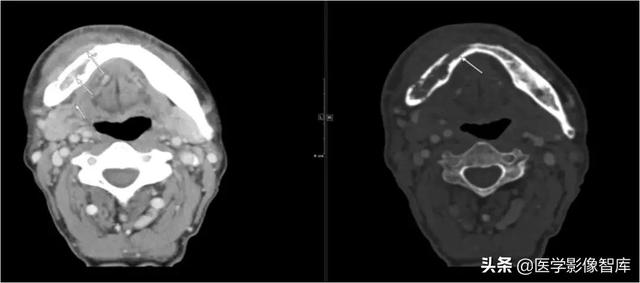

咀嚼肌间隙、颌下间隙、左侧颞下间隙,颊间隙,翼颌间隙

男,55岁,左下后牙反复肿疼1年余,加重1月余,疼痛剧烈伴张口受限,面部肿胀。

咀嚼肌间隙有脓肿形成。